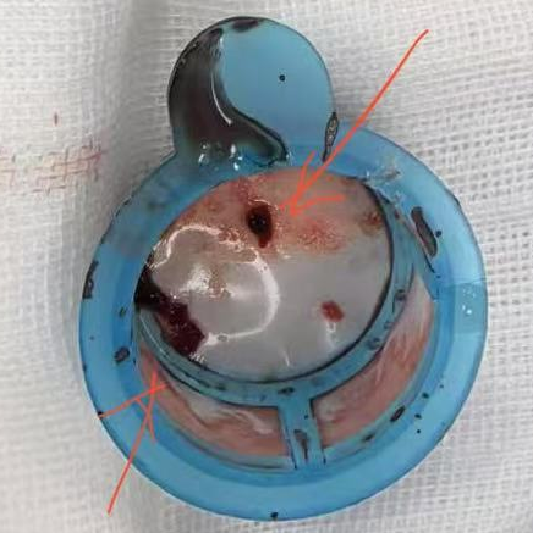

抽吸【例】量|【捷】谈血栓抽吸